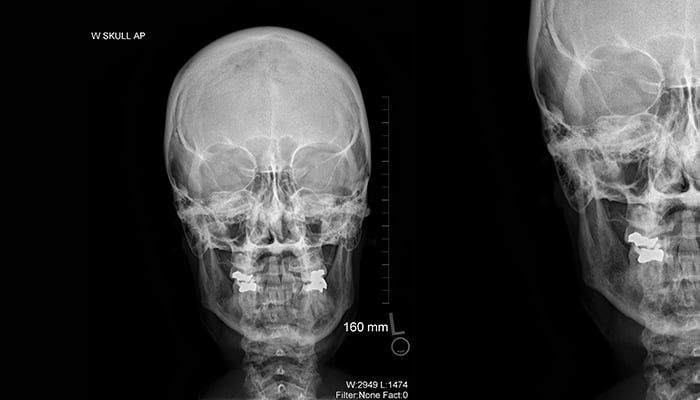

Skull X-ray

X-ray of a skull